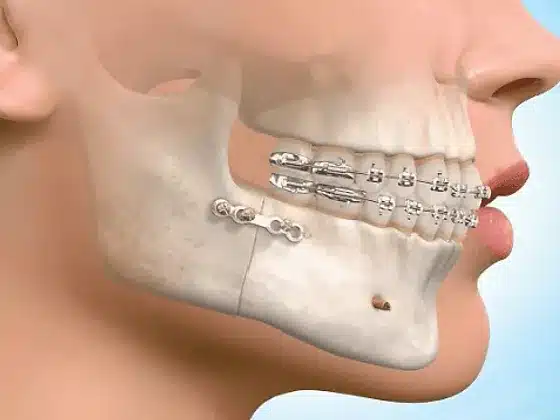

- Craniomaxillofacial trauma,

- Deformed jaw joint cases,

- Lefort-3 distraction for Craniosynostosis case,